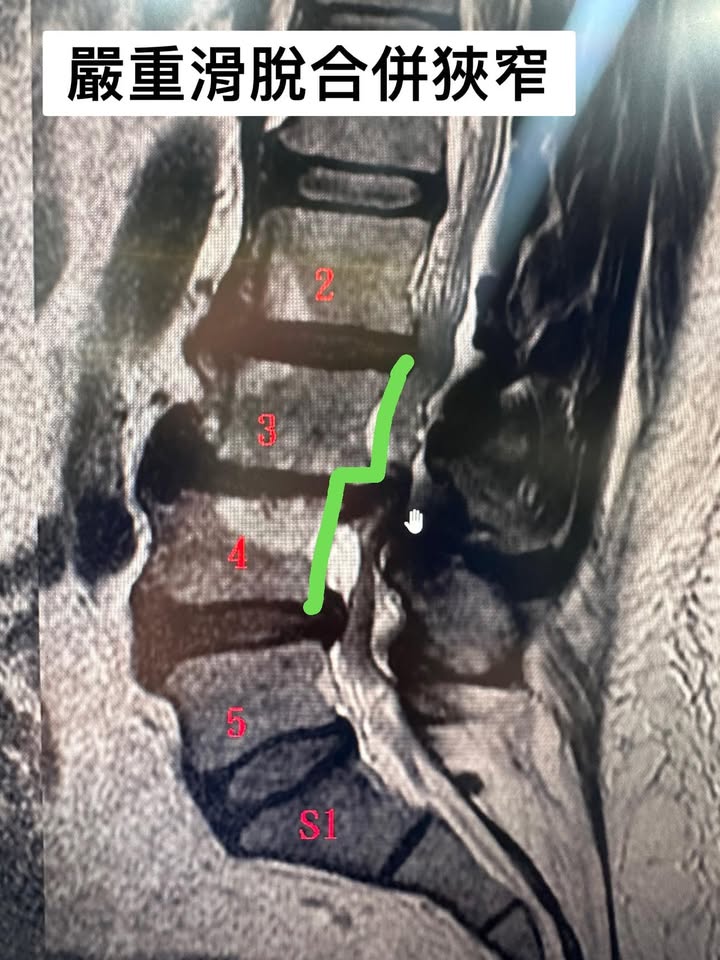

超嚴重的滑脫合併椎管狹窄走路無法超過5分鐘

☑️這個就是我們台語講的龍骨「走山」

🟢說實在的這個患者真的不好處理,年紀也70多歲了,因為他來診所的時候整支腳特別是左腳都沒力,早期都是拿拐杖🩼來門診,所有的護士都可以作證,真的很辛苦的治療將近兩個多月狀況才慢慢改善到最後甚至可以不用拐杖在公園走好幾圈,這中間連我差一點都要放棄,請他去大醫院開刀,因為治療的一開始效果很慢,幾乎治療的前面一個月效果很慢,所以連我也很著急,結果一直到治療第九次以後開始明顯改善⋯⋯⋯

🔵 🌐 治療思維:按照骨科思維,腰椎滑脫的患者就是要固定!除非患者的核心肌群被建立起來,我們使用減壓的方法讓患者的神經根位移,先讓疼痛症狀改善,在教育患者如何建立核心肌群,古典針灸在增強肌力這方面也有幫助,林阿伯一開始的棒式運動只有撐不到10秒,在經過六週的治療後,可以撐到90秒!想當然核心肌群穩定他老人家的韌帶跟肌肉,整個症狀幾乎完全消失!